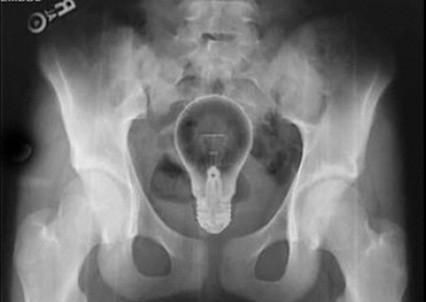

珍藏的图片,希望不要被X掉